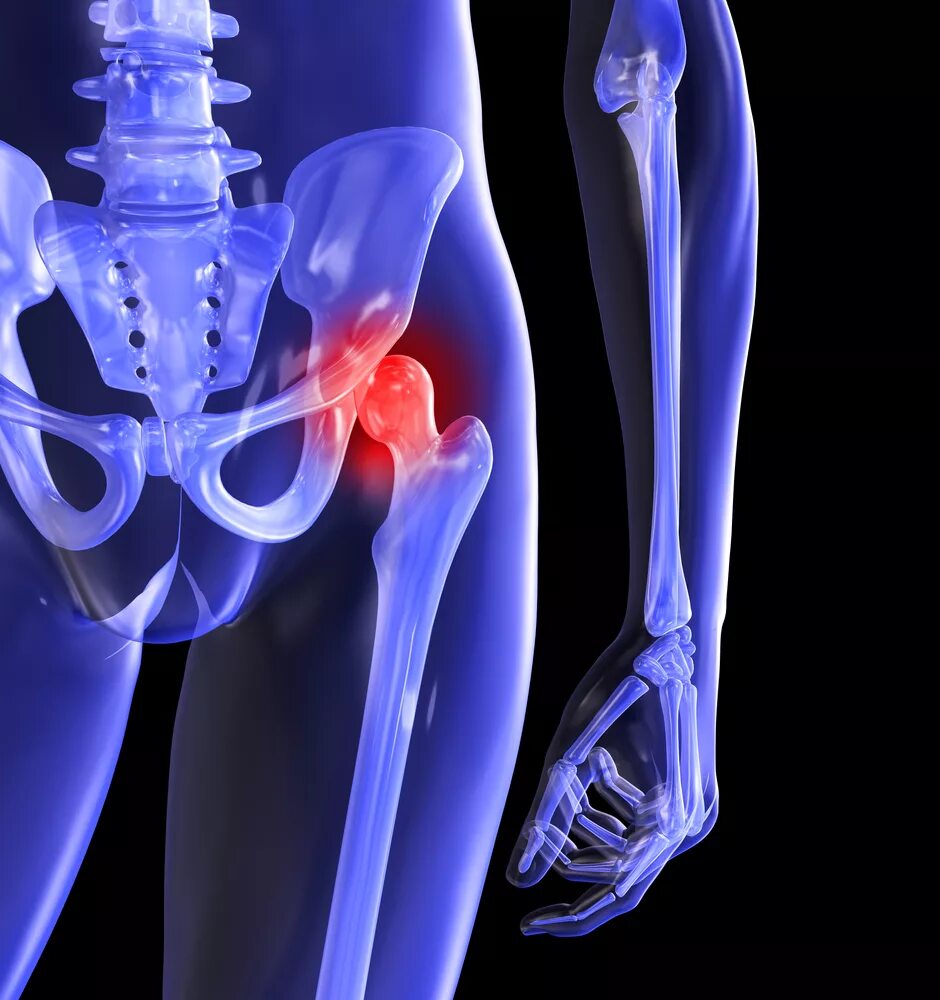

Тазобедренный сустав это